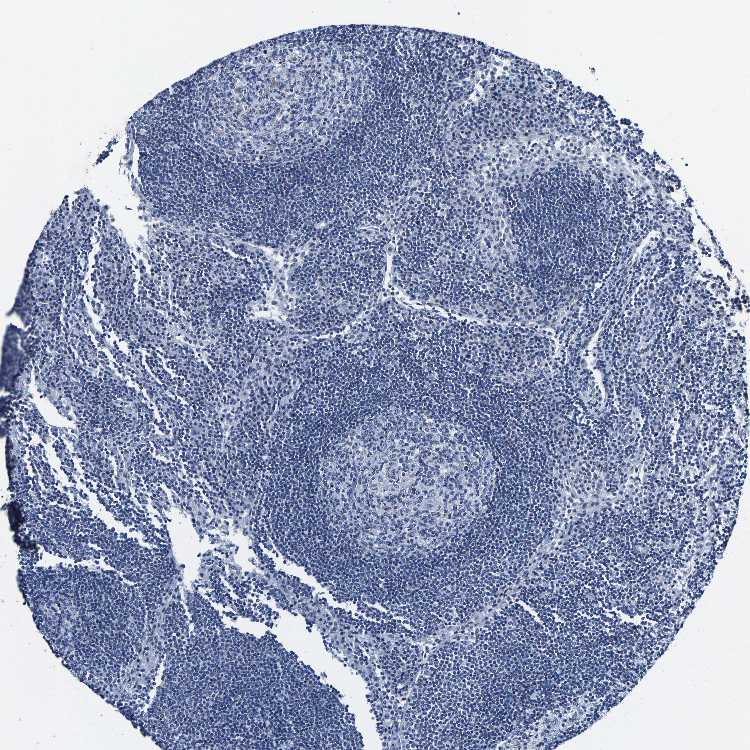

TISSUE PRIMARY DATA LYMPH NODE Show tissue menu

Lymph node

LYMPH NODE - Expression summary

LYMPH NODE - Antibody stainingi

Antibody staining in the annotated cell types in the current human tissue is reported as not detected, low, medium, or high, based on conventional immunohistochemistry profiling in selected tissues. This score is based on the combination of the staining intensity and fraction of stained cells.

Each image is clickable and will lead to virtual microscopy that enables deeper exploration of all samples and also displays staining intensity scores, fraction scores and subcellular localization as well as patient and tissue information for each sample.

Antibody HPA019743Antibody HPA020124

Germinal center cells Not detectedNot detected

Non-germinal center cells Not detectedNot detected